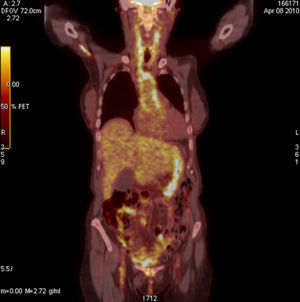

Case 1We present the case of a 43-year-old woman with a history of chronic sinusitis, corneal ulcers and relapsing blepharitis, treated with 30mg of prednisone day after being studied in the infectious diseases unit due to persistent low-grade fever of 37.5°C, where a microbiological origin was ruled out. A few weeks after presenting clinical improvement, her fever returned for 15 days, improving with antipyretics; her blood pressure (BP) levels were 100/60mmHg and she presented paresthesias of her left foot. An electrophysiology study was conducted and showed an electroneurographic pattern of conduction block at the left distal posterior tibial nerve, compatible with peripheral nervous system vasculitis. Laboratory tests showed mild leukocytosis with a small leftward shift, erythrocyte sedimentation rate (ESR) of 97mm (normal values up to 25mm) and C reactive protein (CRP) of 1.22mg/dl (normal to 0.5mg/dl) with negative antineutrophil cytoplasm antibodies (ANCAS). A cerebrospinal fluid study showed pleocytes and lymphocytes. The first clinical suspicion was polyarteritis nodosa (PAN), so we decided to perform a muscle and sural nerve biopsies that were nonspecific. Because of the history of sinusitis, the diagnosis of microscopic polyangiitis or Wegener's granulomatosis (WG) had to be ruled out, which we did after a biopsy of the affected mucosa. At all times peripheral pulses remained present and symmetrical, with no significant differences in BP between the 2 arms; there were no murmurs on auscultation of the aorta or subclavian arteries and the patient did not complain of fatigue or discomfort and presented no claudication. Within 10 days of admission she presented occipital and frontal headache with photophobia and little improvement with analgesic treatment as well as hypertension (160/95mmHg) which responded with the administration of ACE inhibitors. Keeping with our clinical suspicion of vasculitis we conducted a magnetic resonance angiography (MRA) of the aorta (Ao), which showed no abnormalities, a brain MRI which confirmed the existence of pachymeningitis and a thoracoabdominal CT that showed a small infrarenal aneurysm cm2 diameter. Finally, we performed a PET-CT which showed hypermetabolic lesions of the pulmonary bifurcation and the abdominal Ao wall (Fig. 1), which along with gender, age, involvement of large vessels (Ao and pulmonary), the presence of aneurysms, the negativity of ANCAS, the result of the biopsy and exclusion of PAN and GW, very likely led the diagnosis of Takayasu's arteritis (TA) with the added difficulty of performing a biopsy of the affected area.